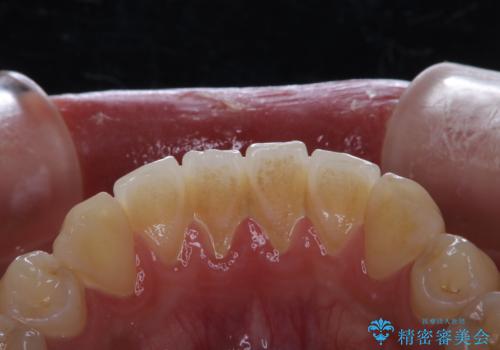

矯正を考えている方のPMTC

治療症例の内容

- 20代男性

- 1日

- 1回

- 矯正治療を考えていて、歯科医院が久しぶりのためまずはクリーニングしたいとのことでした。PMTC60分コースを行いました。

- 1万円+tax費用は治療当時の料金となります